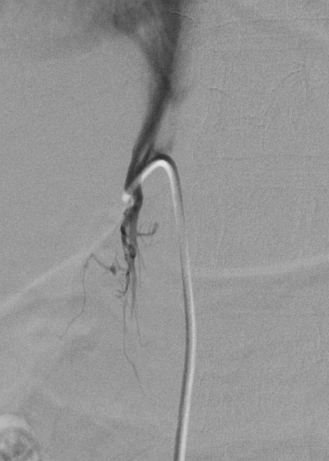

4.2. Adrenal Vein Sampling for Primary Aldosteronism

- Daunt, N. Adrenal vein sampling: How to make it quick, easy, and successful. Radiographics 2005, 25, S143–S158. [Google Scholar] [CrossRef] [PubMed]

- Young, W.F.; Stanson, A.W.; Thompson, G.B.; Grant, C.S.; Farley, D.R.; Van Heerden, J.A. Role for adrenal venous sampling in primary aldosteronism. Surgery 2004, 136, 1227–1235. [Google Scholar] [CrossRef] [PubMed]

- Rossi, G.P.; Auchus, R.J.; Brown, M.; Lenders, J.W.; Naruse, M.; Plouin, P.F.; Satoh, F.; Young, W.F. An Expert Consensus Statement on Use of Adrenal Vein Sampling for the Subtyping of Primary AldosteronismNovelty and Significance. Hypertension 2014, 63, 151–160. [Google Scholar] [CrossRef] [PubMed]

- Makita, K.; Nishimoto, K.; Kiriyama-Kitamoto, K.; Karashima, S.; Seki, T.; Yasuda, M.; Matsui, S.; Omura, M.; Nishikawa, T. A Novel Method: Super-selective Adrenal Venous Sampling. J. Vis. Exp. 2017, 55716. [Google Scholar] [CrossRef] [PubMed]